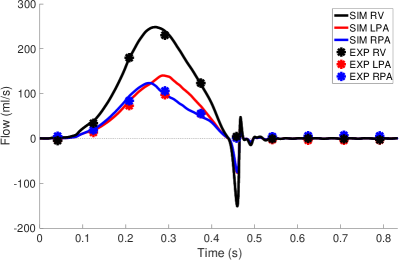

Pressure and flow waveforms from the second cycle in the simulation and the experiment are shown in Figure 7. During systole, the pressures were prescribed. During valve closure, the pressures showed an oscillation as determined by the interaction of the prescribed pressure and resistance (Equation 14). The experimental pulmonary artery pressure had a similar oscillation, but not with precisely the same magnitude or frequency. The RV flow rate closely matched that of the experimental flow. The RPA flow was somewhat greater than the experimental RPA flow, and the LPA flow was somewhat less than the experimental LPA flow. The total experimental flow was not precisely conserved, which is expected given pointwise uncertainty in the 4D flow MRI velocity measurements of 4.7 cm/s, uncertainty in gating of the cardiac cycles and variation from cycle to cycle. The total experimental inflow minus total outflow was up to 27.0 ml/s, which is nearly all experimental uncertainty, as the vessel maintains approximately constant volume. Therefore, it was not possible to simultaneously match all three experimental flow rates. All three simulation flow rates showed a substantial oscillation at the beginning of diastole. Similar oscillations in the experimental flow rates almost surely occurred but could not be captured due to the time resolution of the 4D flow MRI data. We estimated the stroke volume to be 46.11 ml and cardiac output to be 3.32 L/min. Using the maximum flow rate of ml/s and diameter of the valve, 2 cm, as the length scale, we estimated the peak Reynolds number of the flow as

| (19) |

where is the valve orifice area. The Reynolds number is much greater than one and indicates that the flow was in a physically unstable regime.